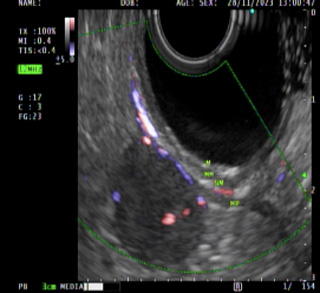

use 02

Imagen 2.Tumor gástrico dependiente de la capa muscular.